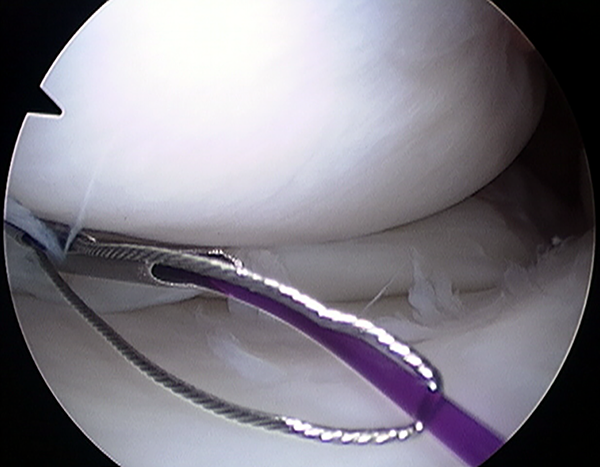

Figura 4:

A través de una de las agujas canuladas se introduce el hilo de sutura PDS nro 1 y a través de la segunda aguja se introduce el alambre lazo, enhebrando a través del bucle del alambre la aguja que contiene la sutura.